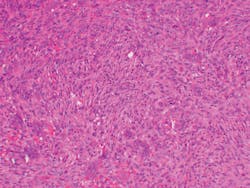

The lesion in Figure 2 shows spindle-shaped mesenchymal cells with focal aggregates of small multinucleated giant cells.

Figure 2: CGCG histology depicting small nucleated giant cells. The stroma is that of fibroblasts and fibrosis. (Photo courtesy of James J. Sciubba, DMD, PhD)